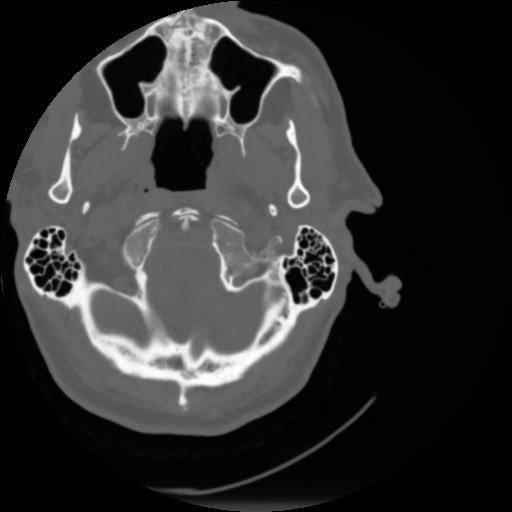

4 CEREBRO,,Vol,0.5,CEREBRO,,